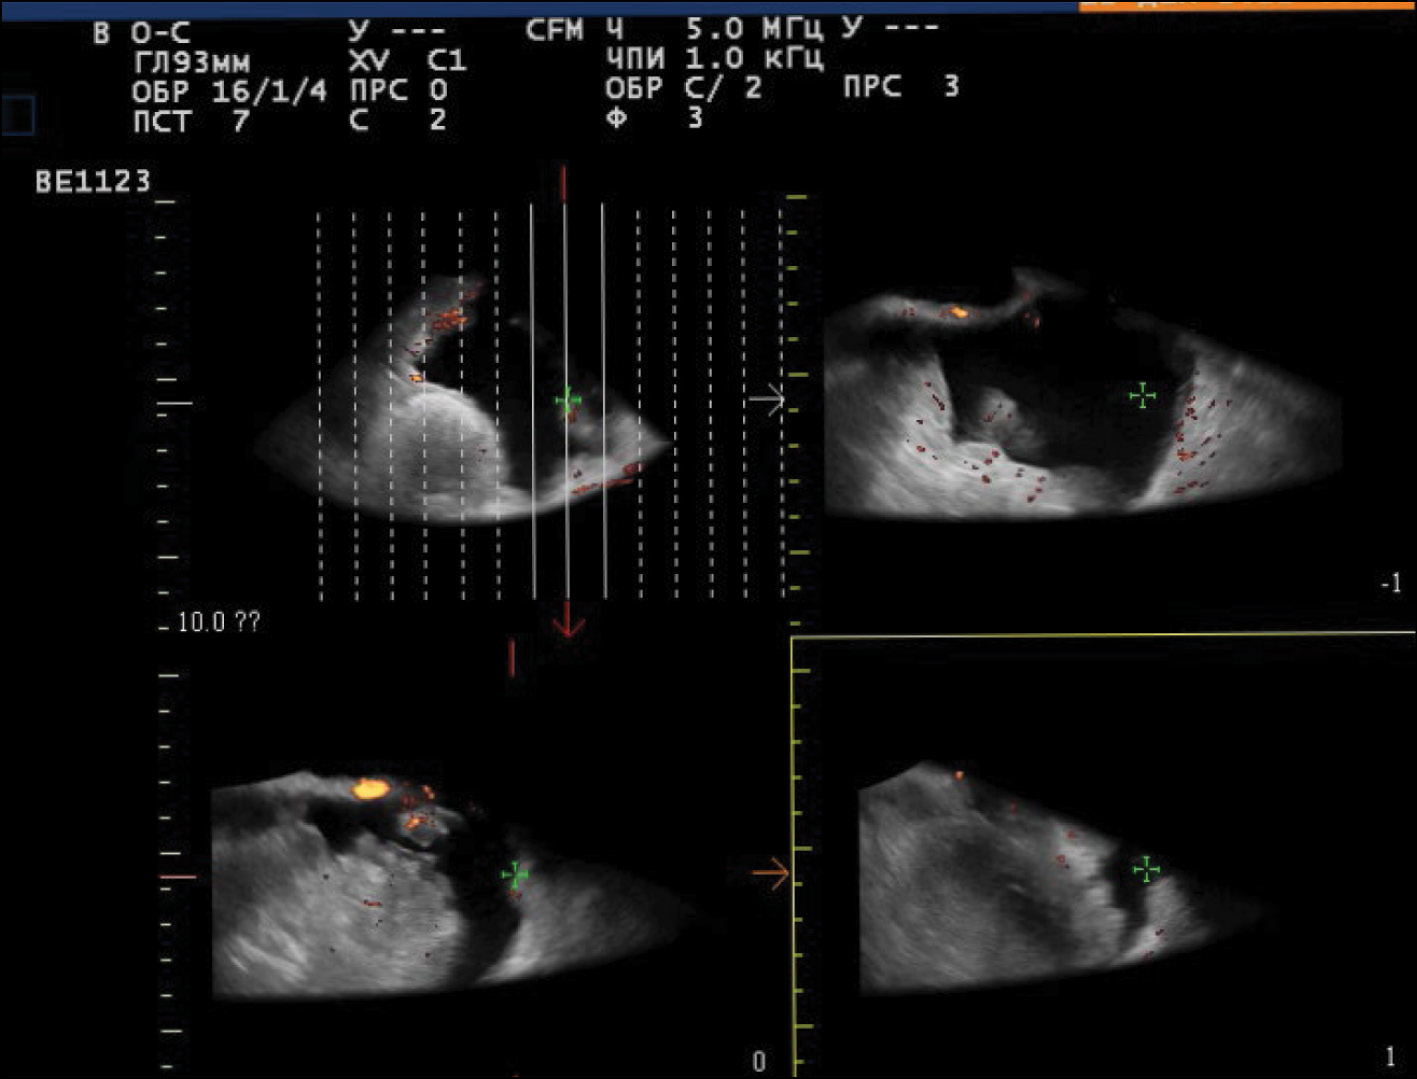

US demonstrated that the recurrent lesion of malignant struma ovarii along the pelvic peritoneum, identified in the presence of ascites, had an iso-hypoechoic structure with fuzzy contours and small size (4–12 mm). The peritoneum of the small pelvis outside the lesion was <4 mm thick; however, 3D angiography and US-CT revealed that even small blastomatous lesions were well vascularized. Blood flow was also present in the 4–5 mm thick structure of the pelvic peritoneum (Figs. 5–7).

Fig. 6. US-CT of the recurrent lesions of the malignant struma ovarii.

Fig. 7. 3D angiography of the recurrent lesions of the malignant struma ovarii in the pelvic peritoneum in the presence of ascites.

To identify specific US signs of malignant struma ovarii, recurrent tumor lesions along the peritoneum of the malignant struma in one patient were compared with recurrent lesions of serous ovarian adenocarcinoma in 12 patients. When comparing the tumor lesions in the retrouterine space, a more pronounced neoangiogenesis was noted in the tumor lesion of the malignant struma ovarii, where the peak systolic velocity (PS) was recorded in small lesions (4–12 mm) and ranged from 2 to 9 cm/s. The maximum vascular resistivity index (RI max) was 0.53. No blood flow was noted in recurrent lesions along the pelvic peritoneum of the serous adenocarcinoma up to 9 mm, and in lesions up to 15–20 mm, PS varied from 2 to 4 cm/s or was <2 cm/s (Figs. 5 and 8).